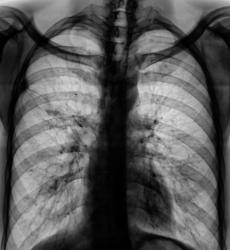

После расшифровку флюорограмм пациента "взяли на контроль". Произведена рентгенография в прямой и правой боковой проекциях.

Всё же я отдал бы предпочтение посттуберкулёзному утолщению плевры, это подкрепляется наличием множества кальцинатов и интесивность тяжестости характерна для фиброза, но ни как для лимфангиита. В большинстве случая имеет место быть выпоту в плевральной полости. Но верификация конечно должна быть на уровне гистологии если есть подозрение.

Пациент, когда-то состоял на учете у фтизиатра, проводилось специфические лечение, хотя - "концов нет". Не нашли ни снимки и карточки. Дело в том, что раньше при ЛПУ было туб. отделение, которое было ликвидировано несколько лет назад, и в процессе ликвидации ликвидировались....

Склоняюсь к посттуберкулезным изменениям. Вероятно очаг был в 3-м сегменте и прилежал к междолевой плевре, отсюда и изменения самой плевры в виде спаек.